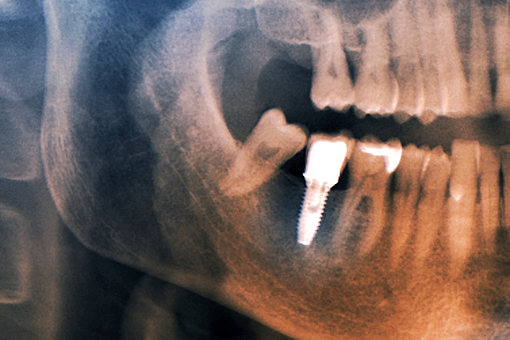

실제 임플란트 치료 사례

레더스스마일치과는 의료법을 준수하며 위 사진의 저작권은 레더스치과에 있습니다.

모든 사진은 환자의 동의하게 기재된 사진입니다.